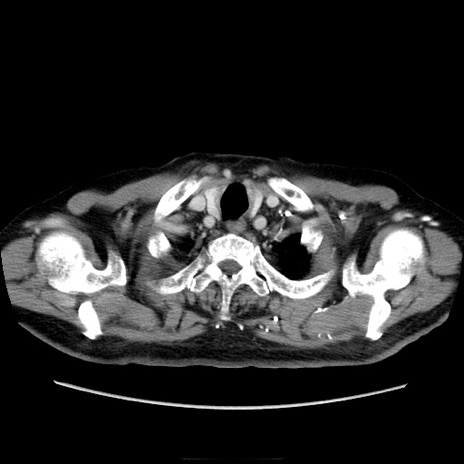

症例21(横断像)

【症例】70歳代男性

【主訴】腹痛

【現病歴】肝硬変・肝細胞癌にてかかりつけの方。約9時間前に食後より腹痛出現。症状が徐々に増悪し、嘔吐出現したため来院。

【既往歴】肝硬変、肝細胞癌(RFA、TACE後)

【身体所見】意識清明、表情苦悶様、BT 36℃、BP 129/78mmHg、P 88bpm、SpO2 97%(RA)、右上腹部から心窩部にかけて圧痛あり、反跳痛なし、筋性防御あり。

【データ】WBC 5800、CRP 0.16